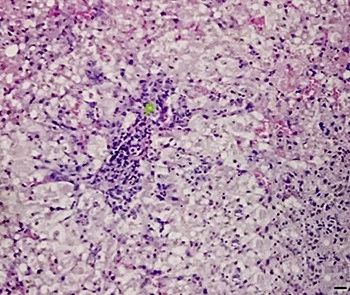

【诊断】根据生活史、临床症状,结合实验室检查(血脂增高,ALP明显升高,高胆红素血症,ALT和AST通常也增高,但增高幅度不大)、组织病理学检查(肝脏活体组织检查)及B超检查 (肝脏回声弥散性增强,肝脏肿大)等,可作出诊断(图12、图13)。

图12 脂肪肝综合征

病理切片示肝细胞脂肪变